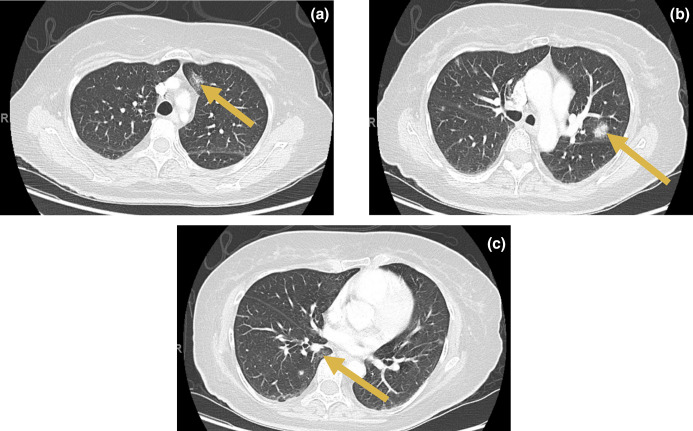

Case presentation: A 62-year-old female renal transplant recipient admitted to hospital with a 2-month history of dry cough and fevers occurring weekly when receiving electrolyte replacement infusions via a Groshong line. Over 2 weeks, blood cultures repeatedly isolated a Gram-positive bacillus solely in aerobic bottles, and this was initially reported as Rhodococcus spp. by the local microbiology laboratory. Chest computed tomography (CT) showed multiple ground-glass lung opacities suggestive of septic pulmonary emboli. As central line-associated bloodstream infection was suspected, empirical antibiotics were initiated and the Groshong line was removed. The Gram-positive bacillus was later confirmed by the reference laboratory as Gordonia sputi via 16S rRNA sequencing. Vancomycin and ciprofloxacin for a duration of 6 weeks were completed as targeted antimicrobial therapy. After treatment, the patient remained symptom-free with marked improvement on repeat CT chest imaging.